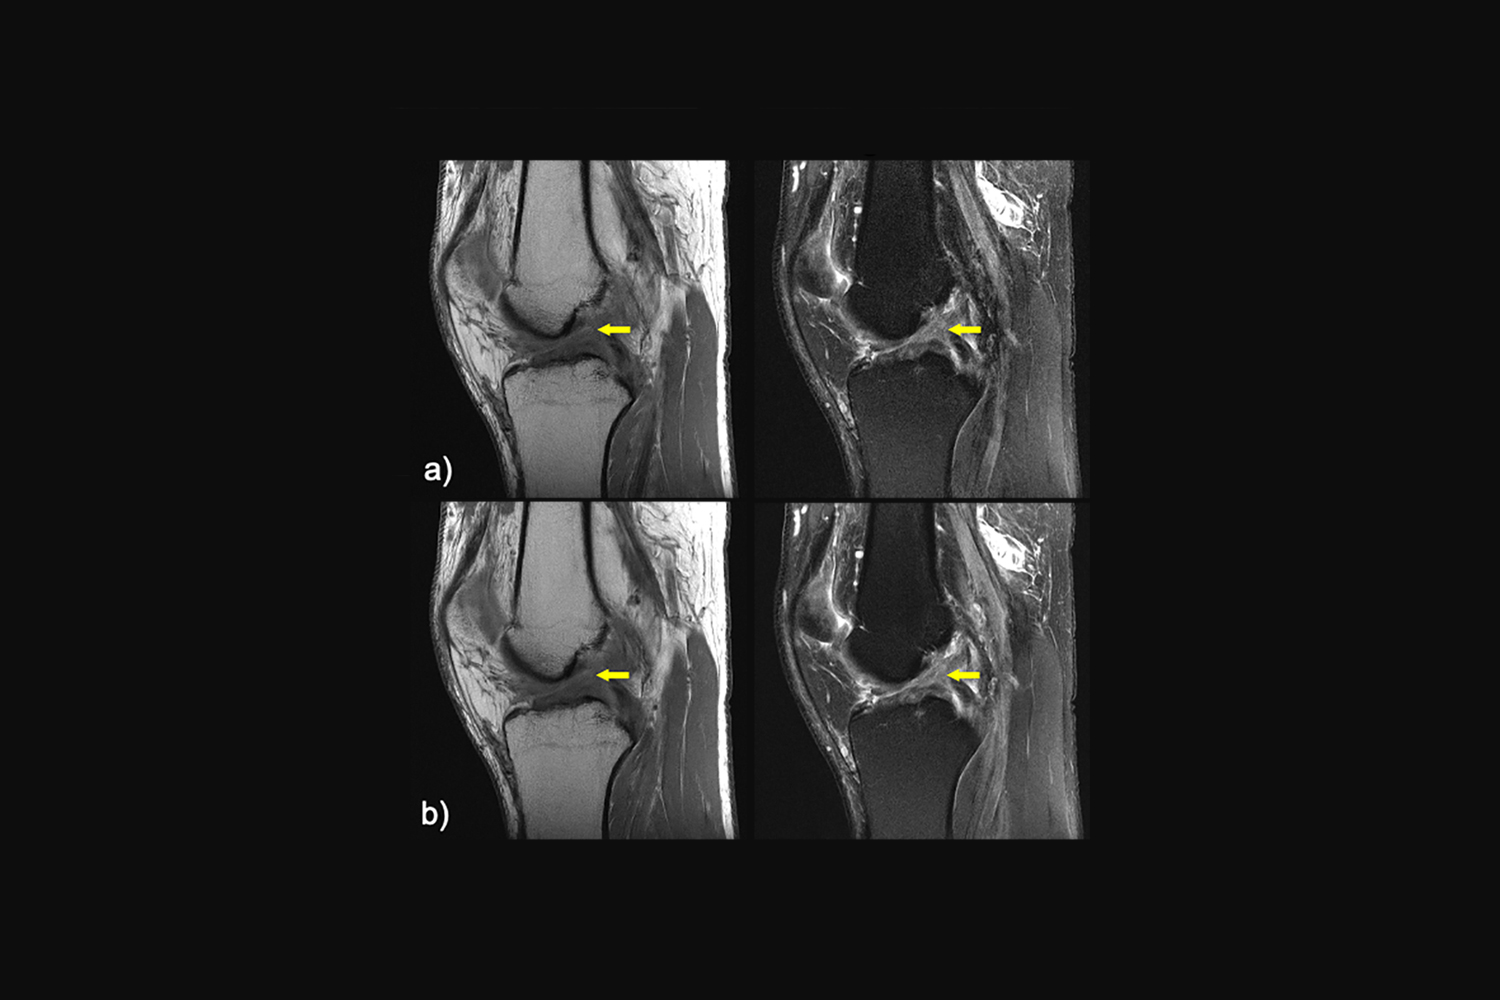

https://nyulangone.org/news/sites/default/files/2023-01/press-release-artificial-intelligence-reconstructs-data-mri-scans.jpg